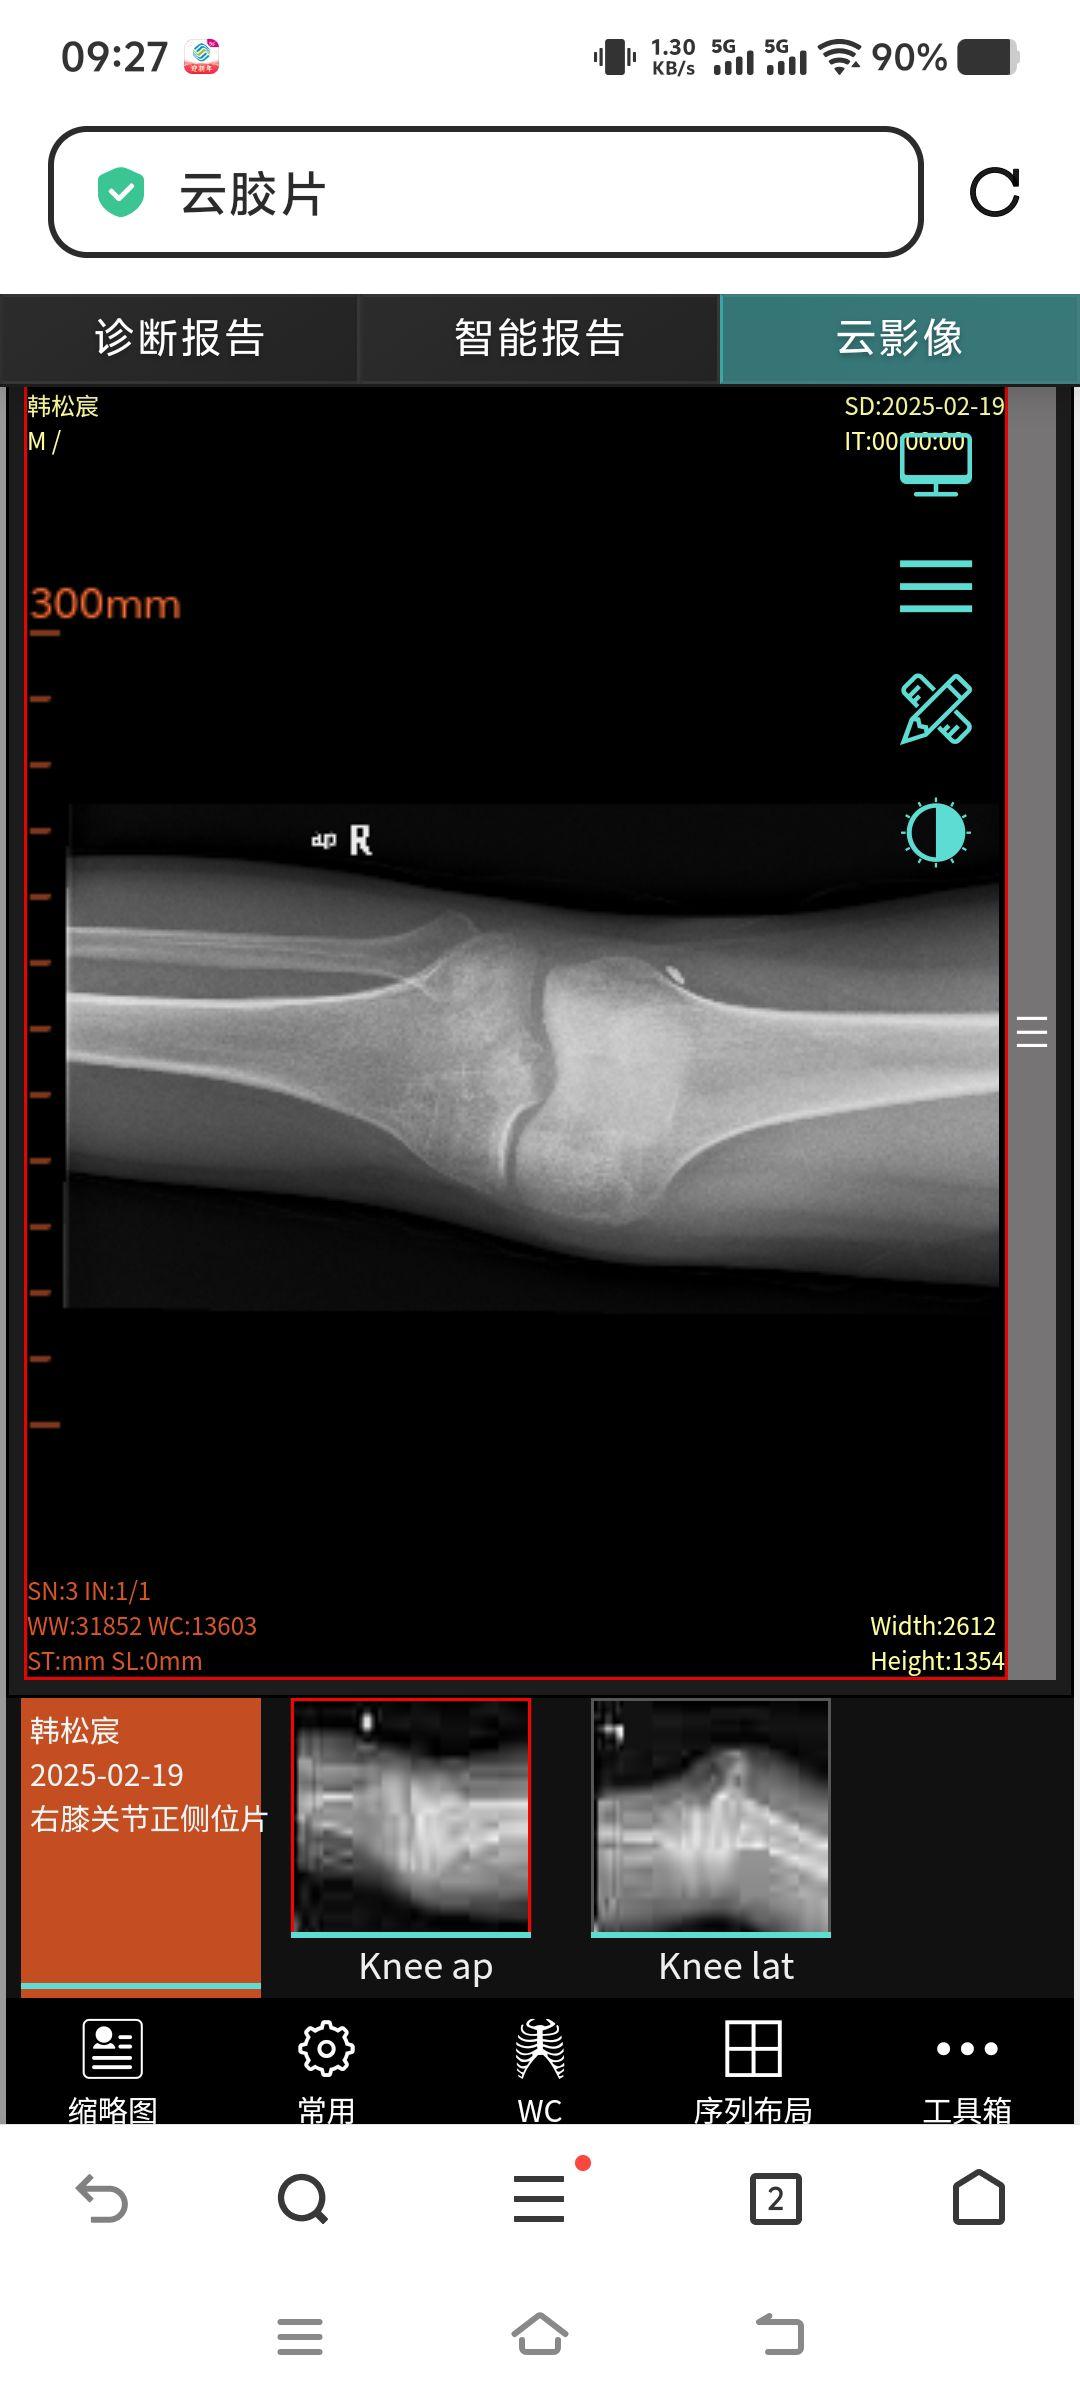

胫骨平台骨折23天

男,22岁,跑步时不慎受伤,诊断为胫骨平台骨折,大家看看现在恢复情况,会有后遗症不?啥时弯腿康复训练合适?

你这不是平台骨折吧,你这个是做的前交叉韧带重建手术,看骨道和带袢钢板位置都很好,术后就可以练习屈膝和股四头肌等长收缩,康复练的好不会有后遗症。